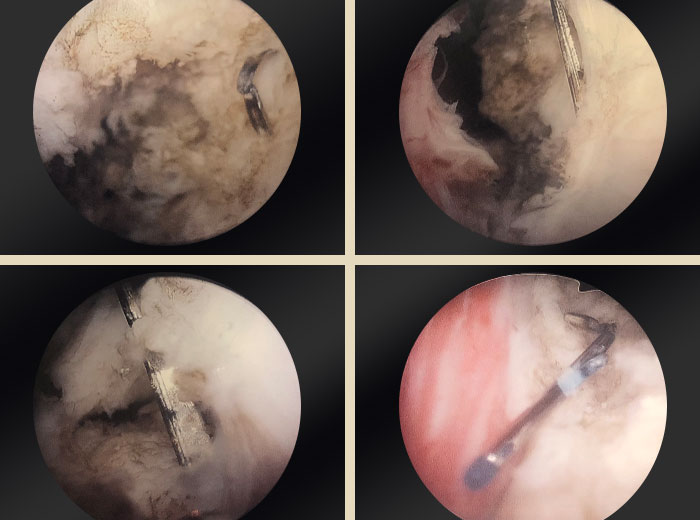

UroLift clips embedded in prostatic tissue

Images provided courtesy of Dr. Ricardo Gonzalez.

4 individual shots of an OR camera zoomed into prostate.

My step-by-step approach involves an enucleation versus vaporization incision technique to remove the clips. Traditionally, we begin with an incision at five and seven o’clock on the undersurface of the lateral lobe, that step is the same. And then the following step would be to make a counterincision on the anterior commissure of that same lobe. So if you do a five o’clock incision under the left lobe of the prostate, then you make a one o’clock laser incision down to capsule at the anterior commissure of that left lobe, you can identify the capsule and use the laser to peel the prostate lobe off of the capsule as you work from one incision towards the other. Working from the one o’clock incision down towards the five o’clock or from five o’clock to one o’clock behind the clip.

If you don’t have a morcellator, you would use the laser to divide that segment into smaller pieces that can be extracted with a grasper after the case, rather than using a morcellator. If you are going to use a morcellator, it’s important to try to remove the metallic parts like the stainless steel luminal side of the clip before morcellating the tissue that you have pushed into the bladder.

The steps to doing a trilobar enucleation for doing a PVP VIT procedure remain the same, but the purpose is to work around the clips to be able to excise them in the tissue, whether it’s en bloc, or in fragments that contain that tissue. In my practice, the most reasonable is to do the PVP VIT technique. The GreenLight laser not only cuts through the prostate tissue efficiently, but can cut through the PET portion of the UroLift implant to allow separation of the luminal stainless steel clip, along with the tissue that’s causing obstruction.

And then that procedure’s repeated on the contralateral side. So when the right lobe is treated, you make the incision at the seven o’clock position and 11 o’clock position and remove the tissue in between those two incisions. So the steps are functionally the same. The goal would be to avoid direct laser contact with the metal of the clip, because that may potentially damage the fiber.

I also do not recommend trying to use the laser to dig out the capsular tab because perforation of the prostate capsule can result in bleeding or may have other consequences for the patient. So I remove the tissue that is causing a problem and remove the inner stainless steel tab, but I do not try to extract the nitinol capsular tab if it’s outside of the prostate capsule.

In some patients with large prostates, the tab that is supposed to be outside of the capsule is actually deployed within the prostate tissue itself. And in those cases, removing the nitinol capsular tab, that is in the lateral lobe, is easily removed and does not become an issue.